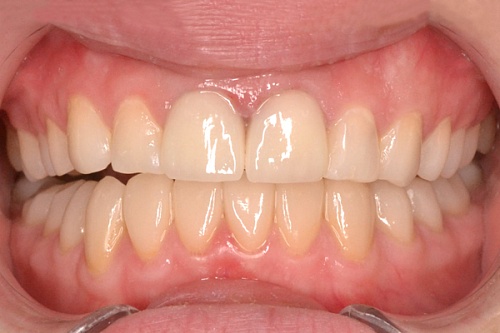

Изменения тканей, которые окружают корни зубов, к сожалению, неизбежны и с возрастом наблюдаются у всех, однако в разном объеме. Так, на развитие пародонтита влияет болезнетворная микрофлора полости рта, которая есть у каждого из нас, но на мы в силах повлиять на ее количество.

Сохранить зубы и пародонт помогает правильная гигиена полости рта дома и в кресле стоматолога, а также своевременное протезирование и имплантация, которые замещают удаленные зубы и равномерно распределяют жевательную нагрузку, не позволяя костной ткани атрофироваться.

Таким образом, по мнению стоматологов, риск возникновения болезней десен на 80% зависит от сознательности самого пациента.